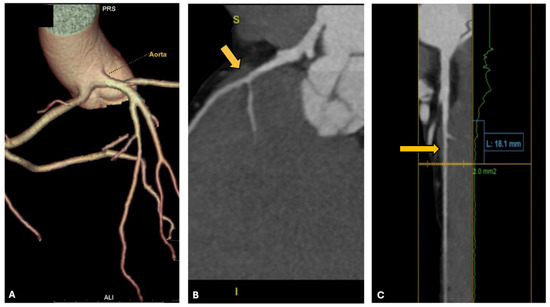

3.5. Case 5: Common Origin of Coronary Arteries from Left Valsalva Sinus with Interarterial Course

| 5 | 31 | Triathlon | Anomalous right coronary artery, myocardial bridge | Asymptomatic, ventricular extrasystoles | No |